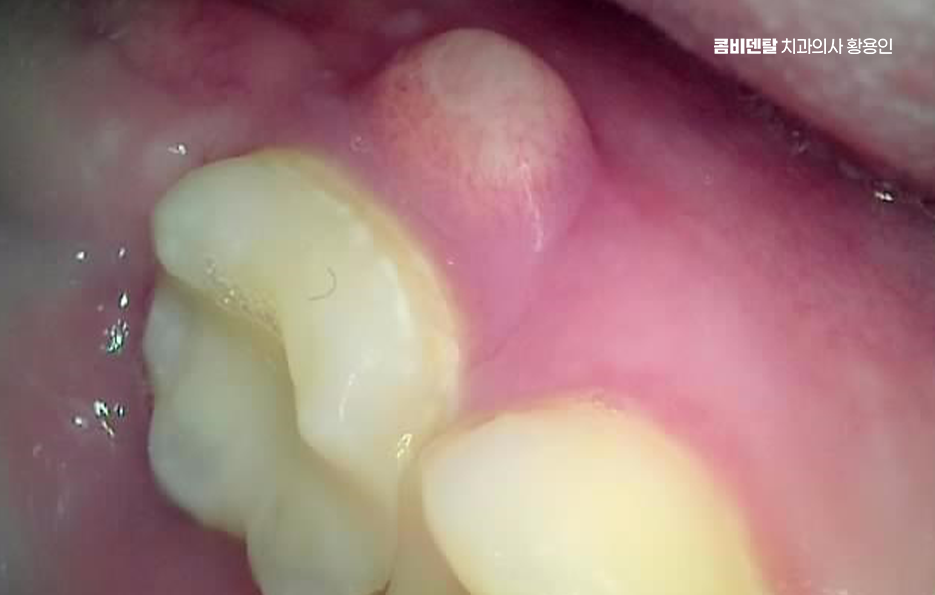

좀더 자세히 원인과 증상에 대해 살펴보면 어금니 뒤쪽은 치아 구조상 칫솔이 잘 닿지 않는 부위라서 음식물 찌꺼기가 남아 있거나 플라그가 쉽게 쌓이게 되는데 치아 사이 공간이 좁고 잇몸이 연약한 부분이라서 세균이 번식하기 쉬운 환경이 만들어지고, 이로 인해 잇몸이 붓거나 염증이 생길 가능성이 커질 수 있었어요

처음에는 가볍게 붓고 불편한 정도지만, 점점 심해지면 통증이 발생하거나, 잇몸이 붉어지고 단단해지면서 눌렀을 때 고름이 나오는 경우도 있어요. 이런 경우 단순한 염증이 아니라 치주염으로 발전할 가능성이 있기 때문에 치과에서 정확한 검진을 받는 것이 필요한 거예요

어금니 뒤 잇몸 부음의 문제는 사랑니가 원인이 되는 경우도 많은데 사랑니는 특히 현대인들의 경우 제대로 나오지 못하고 매복되는 경우가 많으며 완전히 나오지 않은 사랑니는 잇몸 속에서 자라면서 주변 잇몸을 자극할 수 있고, 일부만 노출되면 음식물이 끼면서 염증이 생기기도 하며 특히 어금니 뒤쪽 잇몸이 붓고 지속적으로 불편함을 느낀다면 사랑니로 인한 염증을 의심해 볼 수 있어요. 사랑니로 인한 문제의 경우 단순한 소염제나 구강 세정제로 해결되지 않고, 사랑니를 발치해야 잇몸 염증이 해결되는 경우가 많이 있어요